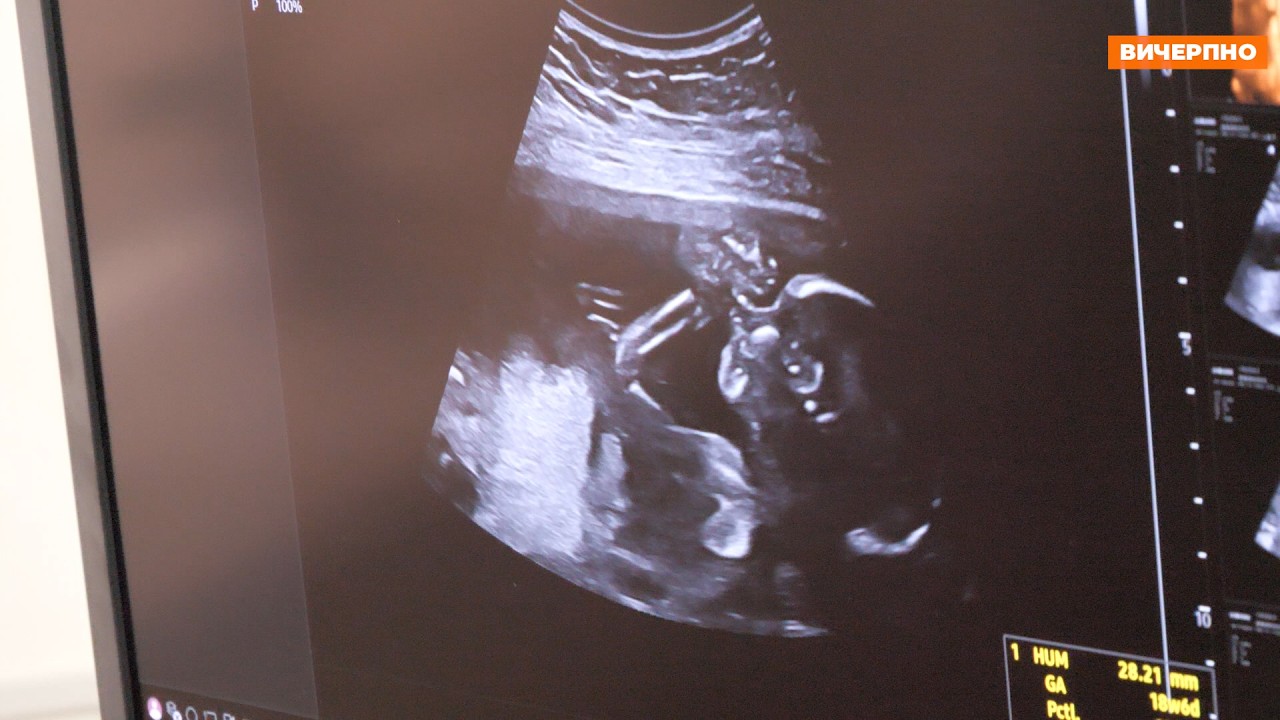

Сучасний УЗД-апарат, яких лише декілька в Україні, запрацював у Черкаському обласному перинатальному центрі (ФОТО, ВІДЕО)

У Черкаському обласному перинатальному центрі нещодавно запрацював УЗД-апарат експертного класу, який дозволить проводити діагностику вагітності на найвищому рівні. Наразі їх лиш декілька на всю Україну.

УЗД-апарат Samsung HERA Z20 у перинатальному центрі встановлений нещодавно, проте вже перші пацієнтки могли відчути його переваги.

Новий апарат ультразвукової діагностики має низку переваг та безліч нових функцій. Зокрема, це новітня інтелектуальна діагностична система преміум-рівня, створена спеціально для акушерства, гінекології та комплексних обстежень.

- надзвичайно чітке зображення без «шумів», добре видно дрібні структури;

- 3D/4D/5D-візуалізація з реалістичним зображенням плода;

- інтелектуальні Al-програми для автоматичних вимірювань і аналізу;

- раннє та точне виявлення особливостей розвитку;

- спеціальні програми для діагностики серця, мозку, кінцівок плода;

Завдяки надзвичайно чіткому зображенню та системі раннього виявлення особливостей розвитку, уже на перших етапах вагітності можна визначити, чи присутні якісь патології плоду.

У даному апараті є повний набір опцій і функцій, які дозволяють максимально побачити найдрібніші деталі розвитку плоду, а отже — надати максимально детальну інформацію майбутнім батькам.

“На сьогодні — це найкращий апарат, який може бути, — відзначає лікарка з УЗД Оксана Береза. — Наприклад, кардіорежим дозволяє побачити найдрібніші дефекти міжшлуночкової аорти, вихід магістральних судин, ми бачимо особливості будови лівого і правого шлуночків, перехресно-магістральних судин. Також тут є режим, який дозволяє нам бачити дрібні судини. Також дуже високі чутливість апарату та роздільна здатність монітору. Це дає нам можливість побачити найдрібніші особливості розвитку дитини. І наші спеціалісти робитимуть все можливе, щоб бачити якомога більше за допомогою цього УЗД-апарату. Оскільки батьки мають право знати якомога більше про стан їхньої дитини”.